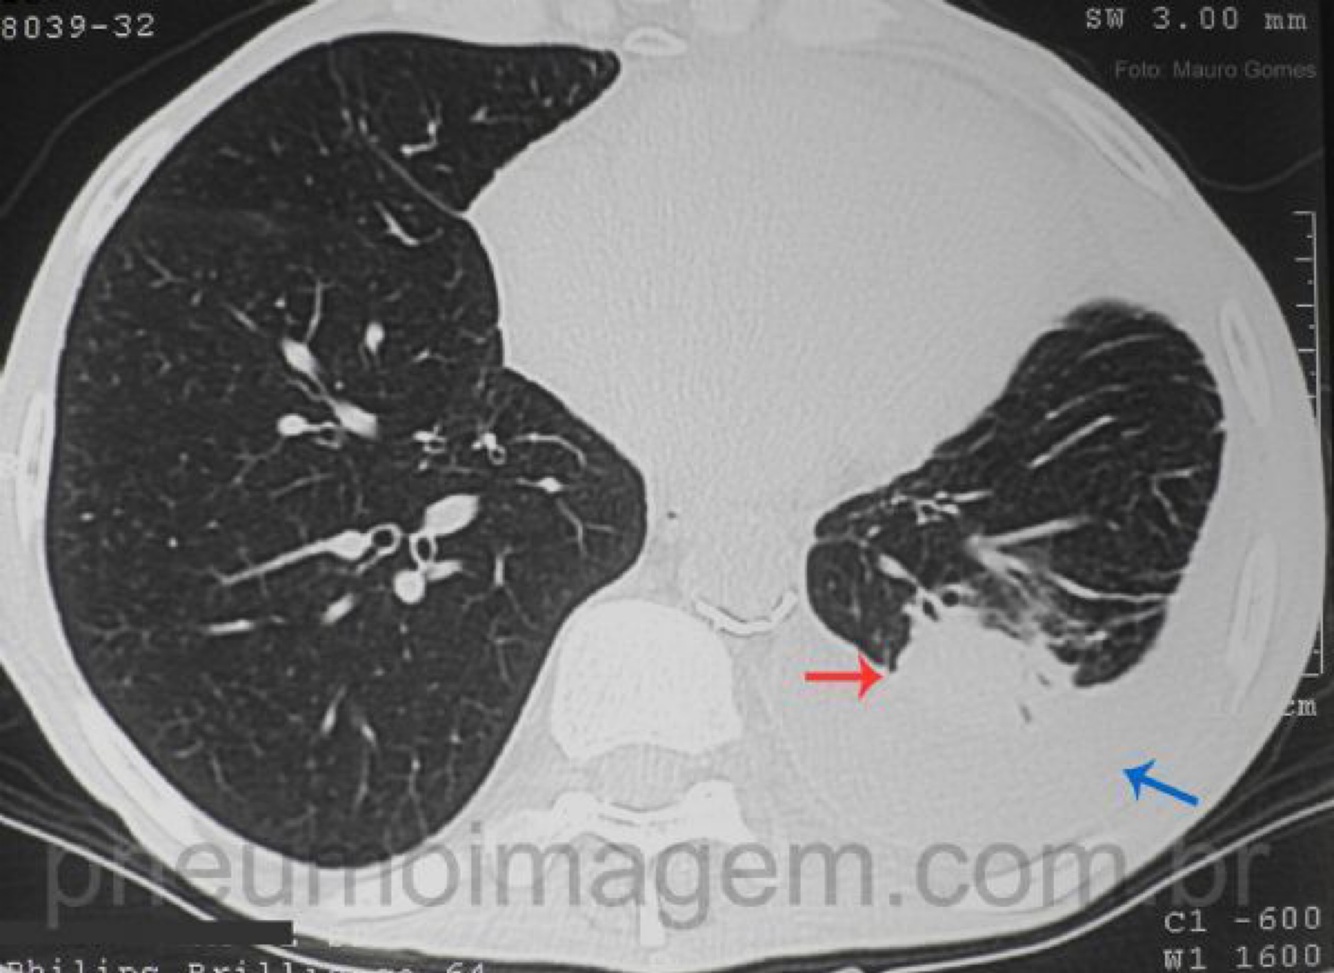

O que caracteriza a atelectasia redonda, um achado típico relacionado ao asbesto?

• Colapso pulmonar focal

• Morfologia arredondada

• Localização na periferia, espaço subpleural

• Associada à doença da pleura

• Distorção dos vasos em cauda de cometa (aspecto típico nos exames de imagem)